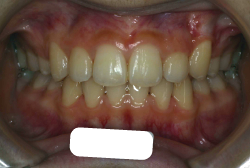

「歯並びの凸凹を直したい」という主訴で来院したケースです。診断の結果、たしかに「叢生」という隙間が足りないと言うことが原因の凸凹症例でした。

しかし、それ以上に問題なのは「前歯の噛み合い方が深すぎる」という症状で、初診の歯の正面写真を見ると下の前歯が全く見えません。こういう症状を矯正学では「過蓋咬合(かがいこうごう)」と言います。過蓋咬合を放置すると、将来的に顎関節に悪影響を与えるとされており、顎関節症の原因因子の一つです。また下の前歯の先端が、上の前歯の裏側の歯茎と強く接触するため、歯周病の原因にもなります。

検査の結果、凸凹が軽症なため非抜歯で矯正すること可能と判断、マルチブラケット装置にて治療しました。治療後は歯並びが綺麗になっただけでなく、噛み合わせ的にも正しい状態が確立しています。